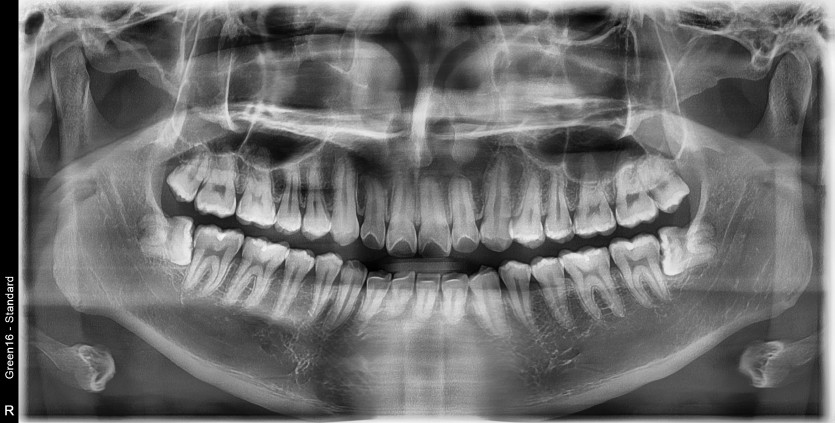

#18,48 사랑니 발치

구강외과 전문의가 당일 발치했습니다.